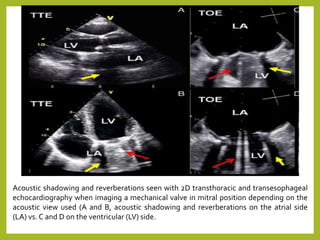

Acoustic shadowing and reverberations seen with 2D transthoracic and transesophageal

echocardiography when imaging a mechanical valve in mitral position depending on the

acoustic view used (A and B, acoustic shadowing and reverberations on the atrial side

(LA) vs. C and D on the ventricular (LV) side.